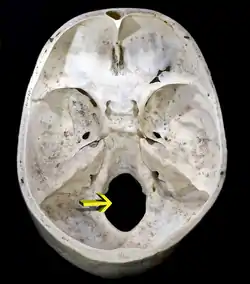

![]() Upper surface of base of the skull. The hole indicated by an arrow is the foramen magnum | |